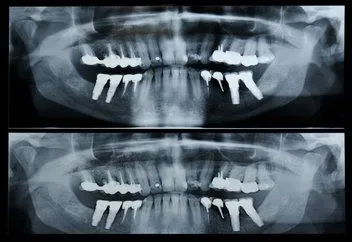

Pan_x_ray.jpg A digital panorex is a very impressive piece of imaging machinery in that it is capable of identifying many issues and structures that a normal x-ray is not. Initially you will sit in a chair with your chin on a small ledge. Once positioned in the machine, it will rotate around your entire head taking a full 360 degree view of the teeth, head, sinuses and bones.

The ability to view the full structure of your head as a whole is very informative to the dentist. It will allow us to see any potential problems and make sure that everything is functioning as it should be. The panorex is capable of viewing location and eruption of wisdom teeth, specific types of structural problems, TMJ condition, infections or asymmetry among many others.